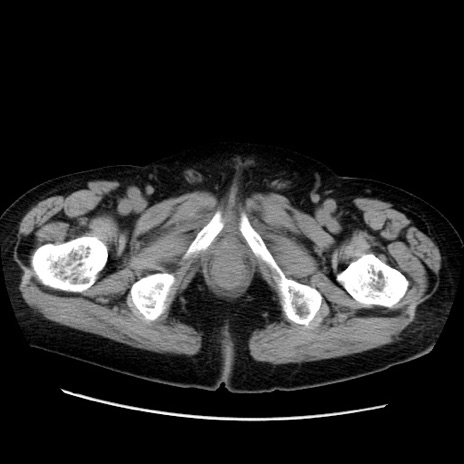

症例21(横断像)

【症例】70歳代男性

【主訴】腹痛

【現病歴】肝硬変・肝細胞癌にてかかりつけの方。約9時間前に食後より腹痛出現。症状が徐々に増悪し、嘔吐出現したため来院。

【既往歴】肝硬変、肝細胞癌(RFA、TACE後)

【身体所見】意識清明、表情苦悶様、BT 36℃、BP 129/78mmHg、P 88bpm、SpO2 97%(RA)、右上腹部から心窩部にかけて圧痛あり、反跳痛なし、筋性防御あり。

【データ】WBC 5800、CRP 0.16